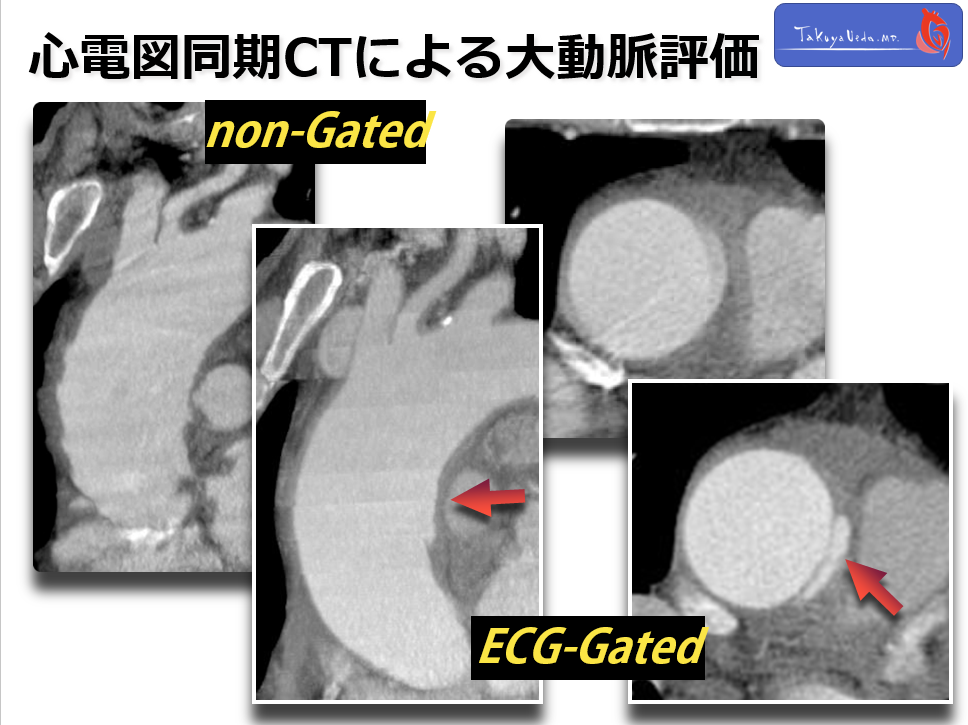

On the next day, the patient still presented unstable chest pain. So, we performed CT again and this time we used ECG-gated technique.

The image is free from the motion artifacts on the ascending aorta.

◆ Here, CT revealed small intimal tear on the ascending aorta which has been hidden behind the artifact.

Such detailed information on Asc. Ao is very important as it may change the surgical strategy.